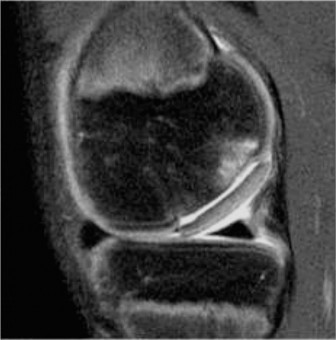

The patient responds well to a period of nonoperative management and returns to sporting activity. He is playing basketball when he has acute onset of pain, swelling, and decreased range of motion after an awkward landing. Plain radiographs are unremarkable, and a repeat MRI (Fig. 10–25) is obtained.

Figure 10–25

The correct answer is (D). The patient has an unstable lesion on MRI which is acute; therefore every attempt should be made to salvage the lesion. The ideal treatment would be fixation of the lesion although the determination for treatment cannot be made until it is examined arthroscopically. If the lesion is not deemed stable during arthroscopy, then drilling would be a reasonable option (and can be combined with fixation). If the fragment is nonviable, microfracture would be a reasonable option to stimulate fibrocartilage formation as long as the donor site is not too large. Fragment removal and chondroplasty is not ideal for a young patient; particularly one who is engaged in sporting activities. Every attempt should be made to salvage the lesion and/or stimulate new cartilage formation if the fragment is unsalvageable. The lesion is shown arthroscopically (Fig. 10–26). The appropriate treatment option is: